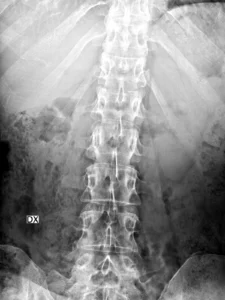

Radiología

Radiografías AP y lateral de columna lumbar, incluye los segmentos dorsales distales. Fractura con reducción de la altura, a predominio anterior, de los cuerpos de D12 y L1, mejor visualizada en la proyección lateral. Irregularidad del ángulo anterosuperior en ambos niveles y probable protrusión del muro posterior de L1 hacia el canal.

Hallazgos principales en Rx:

- En la proyección lateral se identifica pérdida de altura del cuerpo vertebral de D12 y L1, predominante anterior, compatible con fractura por compresión.

- Puede determinar discreta cifosis segmentaria en la unión toracolumbar.

- Alteración del muro posterior o trazo vertical sugerente de fractura más compleja (dato que suele requerir TC).

Comentario didáctico: La Rx puede detectar la fractura y orientar el nivel, pero subestima con frecuencia el compromiso del muro posterior, el canal y los elementos posteriores.